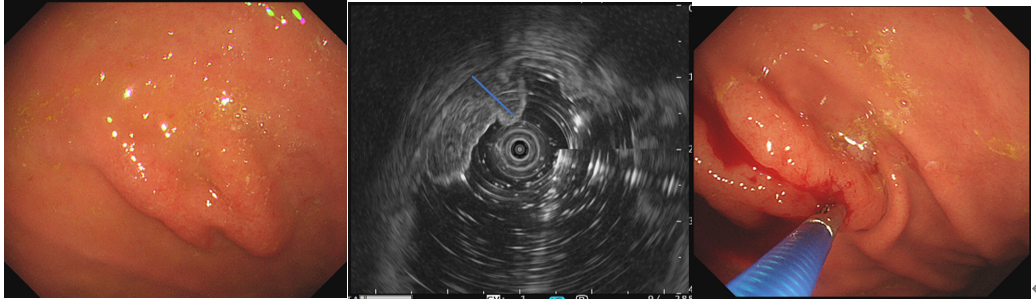

2、消化道肿瘤的分期将探头放置在肿瘤表面进行扫描,可以判断肿瘤浸润的深度、范围、及与周围邻近器官的关系,并判断周围血管和淋巴结侵犯情况,为治疗方案的制定提供依据。

食管癌分期3、胃肠道淋巴瘤的诊断胃肠道淋巴瘤侵犯的层次常常较为深在,超声内镜可以观察病灶处层次,测量受累管壁的厚度,指导深挖活检取材的部位,并观察周围淋巴结的情况。

胃体淋巴瘤超声内镜检查并深挖活检4、胰腺疾病的诊断超声内镜扫查胰腺实质,可以发现B超和CT无法发现的微小病变,还可以对病灶部位进行超声内镜引导下细针穿刺活检(EUS-FNA)。除了肿瘤本身,对周围淋巴结、器官的扫描可以辅助疾病分期。